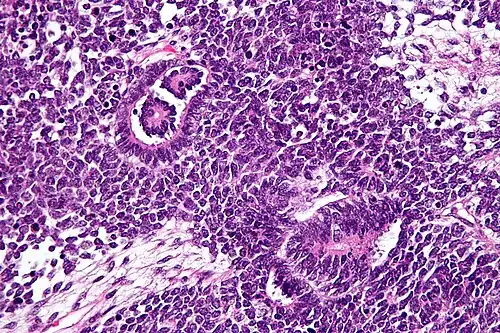

Patológicamente, un nefroblastoma consta de tres elementos:

- Blastema: una masa de células indiferenciadas capaces de crecimiento y regeneración en los órganos o partes del cuerpo, normalmente se encuentran en las primeras etapas de un organismo de desarrollo embrionario, y en la regeneración de tejidos, órganos y huesos.

- Mesénquima: un tipo de tejido conjuntivo reticular, que es de origen mesodérmico y situada en el mesodermo embrionario.

- Epitelio: el grupo de células que alinean las superficies del tumor.

El tumor de Wilms es un tumor maligno que contiene blastema metanéfrico, epitelio y estroma. Es característica su presencia en los glomérulos y túbulos renales rodeado por un estroma celular. El estroma puede incluir músculo estriado, cartílago, hueso, tejido graso y tejido fibroso. El tumor suele comprimir el parénquima renal normal.

El componente mesenquimal puede incluir células que muestran diferenciación rabdomioide, el cual puede por sí mismo mostrar elementos de malignidad: nefroblastoma rabdomiosarcomatoso.